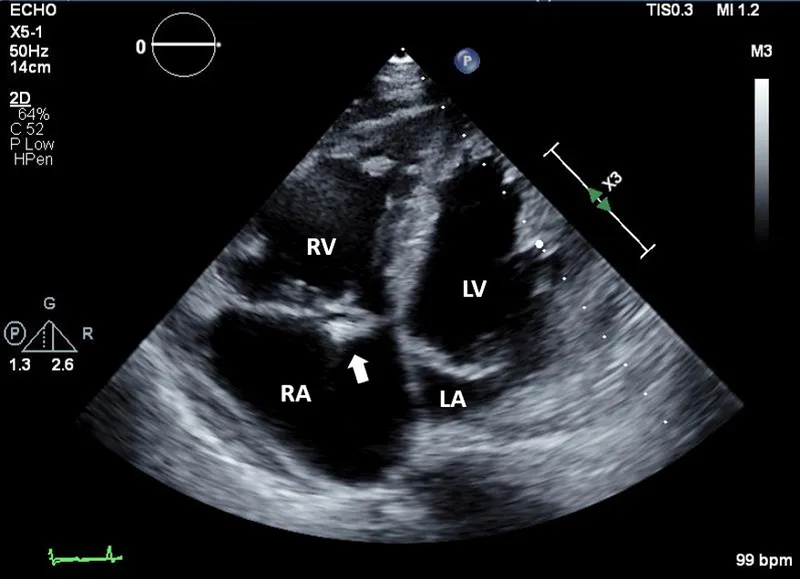

Echocardiography stands as the first-line imaging workhorse, providing real-time visualization of cardiac structure and function without radiation exposure. Transthoracic echocardiography (TTE) achieves diagnostic accuracy exceeding 85% for valvular pathology and 90% for regional wall motion abnormalities, while transesophageal echocardiography (TEE) elevates sensitivity to >95% for posterior structures, vegetations, and atrial appendage thrombi.

Transesophageal echocardiography overcomes TTE limitations through proximity to posterior cardiac structures, eliminating interference from lung, bone, and adipose tissue. TEE becomes essential when TTE image quality proves inadequate or when superior spatial resolution alters management.